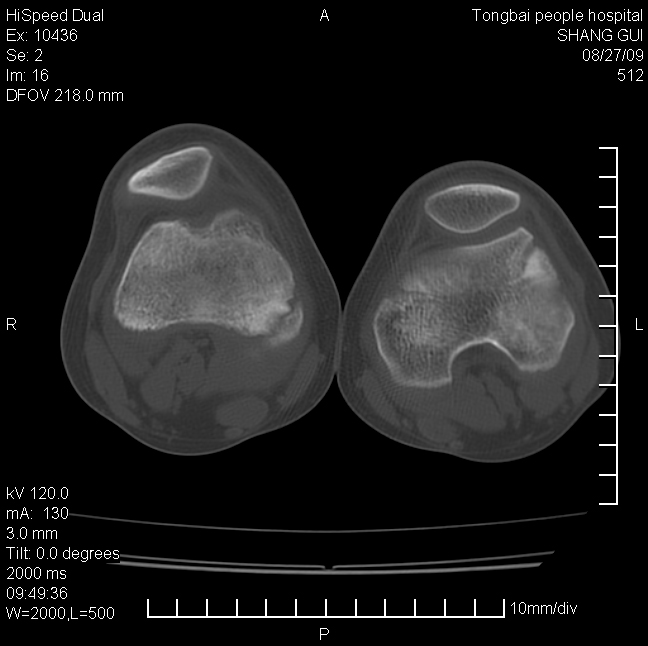

女,12岁。无意发现股骨下端隆起。局部皮肤颜色,温度无异常。

考虑右股骨下端骨纤维结构不良;不排除非骨化性纤维瘤。

不能排除,其实平片更直观。宽基底骨软骨瘤皮质与骨干皮质相连,髓腔与髓腔相通,骨纹理走行方向一致,部分软骨帽可有钙化,本例病变内“磨玻璃状、多囊状改变”比较符合骨纤。